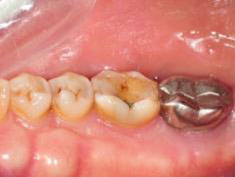

術後一年之全口X光片, #37近心側可見明顯骨充填與放射線密度增加。 牙周再生手術完成一年後追蹤,全口牙齦發炎狀況改善,牙周組織呈現健康狀況。#37金屬燒附陶瓷牙冠製作完成。